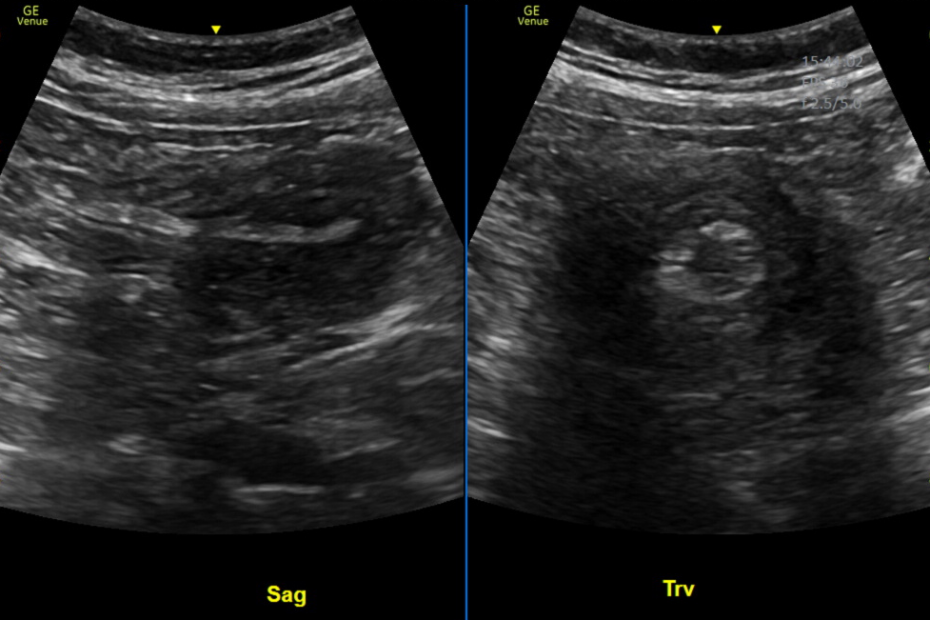

Intussusception